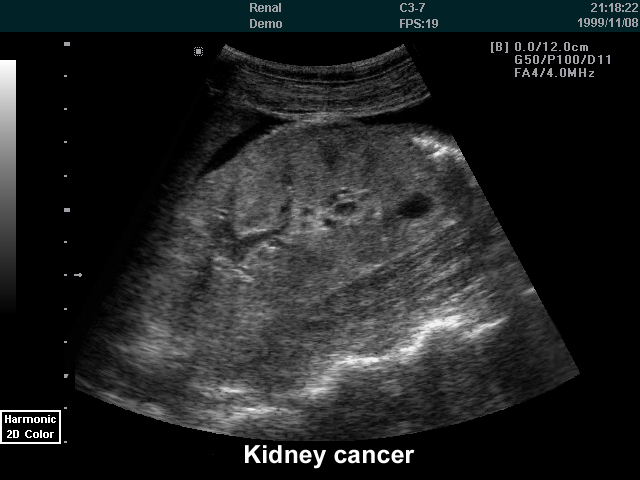

Renal cell cancer Renal cell cancer is a disease in which malignant (cancer) cells form in tubules of the kidney. Renal cell cancer (also called kidney cancer or renal adenocarcinoma) is a disease in which malignant (cancer) cells are found in the lining of tubules ... Get Doc

1 What is kidney cancer? Renal cell carcinoma (RCC) is the most common kind of kidney cancer.1 Normally, your kidneys filter your blood and excrete waste in urine. ... Fetch Full Source

Freezing Kidney Cancer: Hot Treatment May Become New Gold ...

About Kidney Cancer Kidney cancer is the eighth most common cancer in men and the tenth in women. The most common type of kidney cancer is renal cell carcinoma, which forms in the lining of the renal tubules in the kidney ... Retrieve Full Source

Interventional Radiology Treatments For Kidney Cancer

Interventional Radiology Treatments for Kidney Cancer Kidney cancer is the eighth most common cancer in men and the tenth in women.1 The Symptoms The incidence of kidney cancer is on the rise. Fortunately, the availability of modern ... Fetch Doc